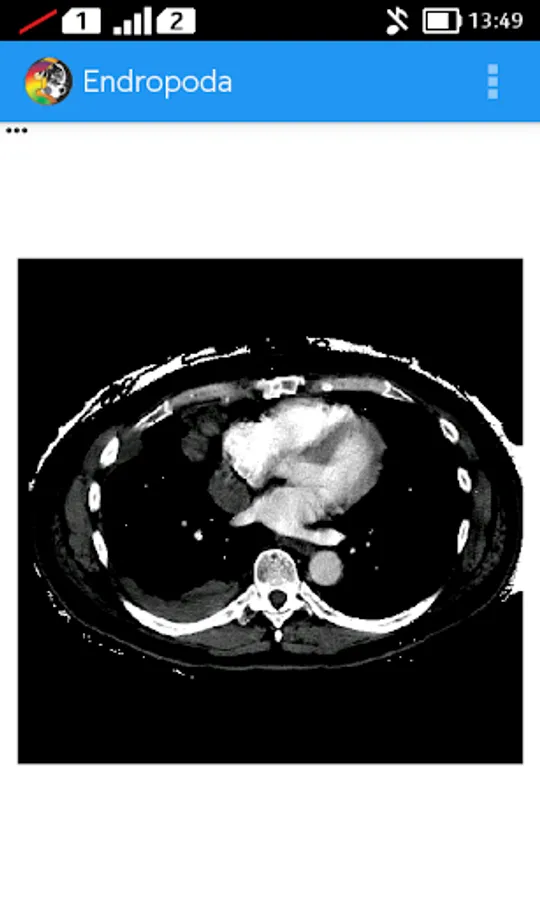

- HU mode : In this mode we can set the window width and window level of CT-Scan image to produce higher contrast higher contrast for certain organ, so it will be displayed better than another organ its surrounding. The basic principal of window technique is based on CT number. Where is CT number is a value related to attenuation coefficient of certain organ that can be used to distinguish an organ from another based on their attenuation coefficient.